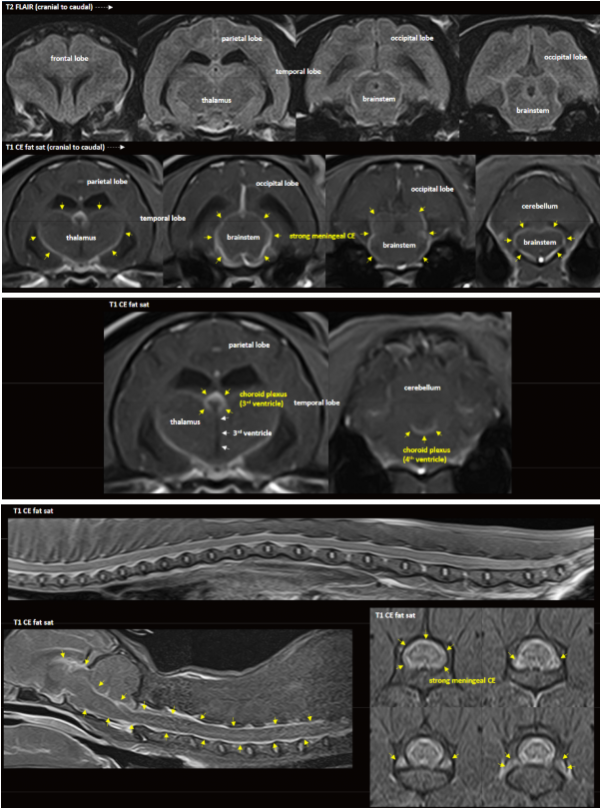

아이의 증상과 신경학적 소견을 바탕으로

뇌·흉요추 MRI 검사를 진행하였고,

영상 소견상 고양이 전염성 복막염이 강하게 의심되었습니다.

▪ MRI상 수막염 + 맥락총염 + 초기 뇌실막염/뇌실염 소견이 함께 관찰됨

▪ 환자의 어린 연령을 고려할 때 → FIP(고양이 전염성 복막염) 중 신경형 FIP 의심

이에 따라 고양이 전염성 복막염 신약 주사 치료를 즉시 시작하였습니다.